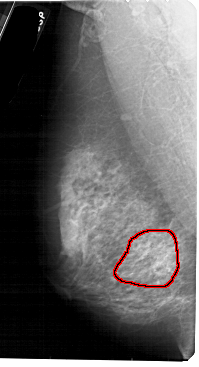

FILE: A_1885_1.LEFT_MLO.OVERLAY

TOTAL_ABNORMALITIES 1

ABNORMALITY 1

LESION_TYPE CALCIFICATION TYPE PLEOMORPHIC DISTRIBUTION SEGMENTAL

ASSESSMENT 4

SUBTLETY 2

PATHOLOGY BENIGN

TOTAL_OUTLINES 1

BOUNDARY

LEFT_MLO LINES 5491 PIXELS_PER_LINE 2971 BITS_PER_PIXEL 12 RESOLUTION 43.5 OVERLAY